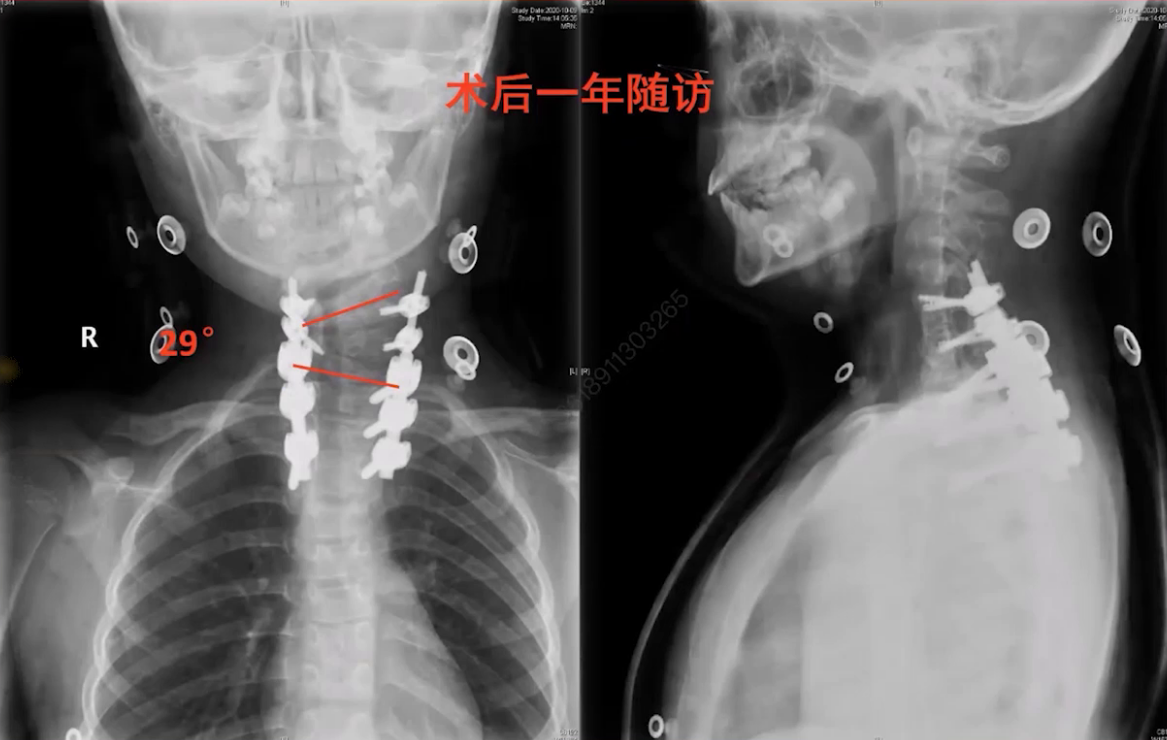

术后局部弯曲从50度改善到28.5度,头颅倾斜角和下颌倾斜角分别改善到2度和1度,肩部平衡从2.8cm改善到0.9cm,矫形效果良好,但出现矢状位平衡偏差,冠状位失衡从6mm增加到36.8mm。考虑是患儿头颅倾斜时间长,突然摆正头后身体需通过倾斜维持原有平衡姿势,后期通过代偿和步态矫正有望改善。

(2)术后一年随访发现,弯度几乎无变化,头正肩平,冠状面失衡较术后早期有所改善。